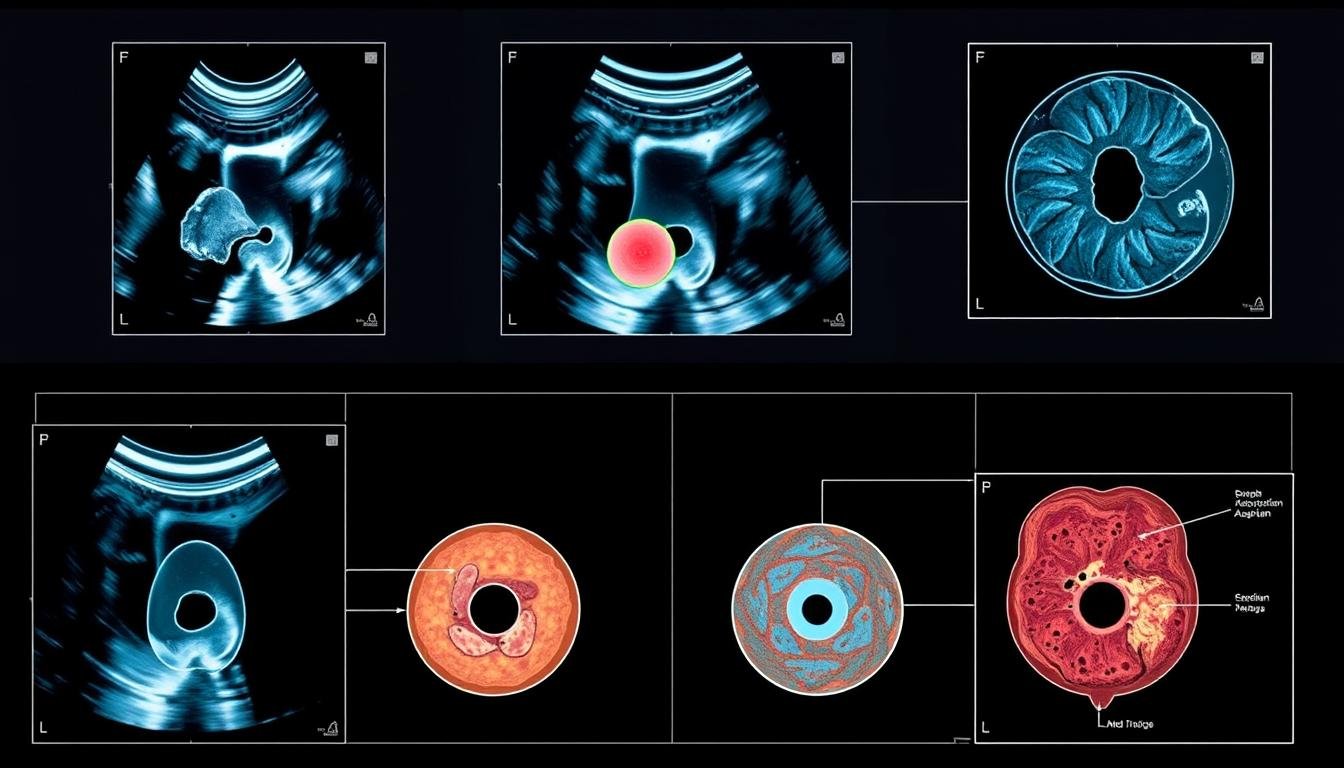

L’imagerie par résonance magnétique existe sous deux formes principales : champ fermé et champ ouvert. Chaque type est conçu pour répondre à des besoins spécifiques, offrant des avantages distincts selon les situations médicales.

IRM à champ ouvert

L’IRM à champ ouvert, quant à elle, est dotée d’un aimant permanent de 0.3 à 1.2 Tesla. Elle est particulièrement adaptée aux patients souffrant de claustrophobie ou nécessitant un accès facile pendant l’examen. Son coût est réduit de 30 % par rapport aux systèmes fermés, ce qui en fait une option attractive pour les cliniques.

Elle est souvent utilisée en pédiatrie et en orthopédie peropératoire. Cependant, elle présente des limites en résolution pour les petites structures. Les avancées récentes incluent des systèmes hybrides combinant champ ouvert et ultrasons, améliorant ainsi la précision.

Cette technique est également utilisée pour étudier les organes abdominaux, comme le foie ou les reins, offrant une résolution en contraste dix fois supérieure à celle d’un scanner.

Comparée à l’échographie ou à la tomographie par émission de positons (TEP), l’IRM offre une meilleure résolution des tissus mous. Elle est également utilisée en combinaison avec la spectroscopie pour étudier les processus métaboliques, ce qui en fait un outil polyvalent en médecine.